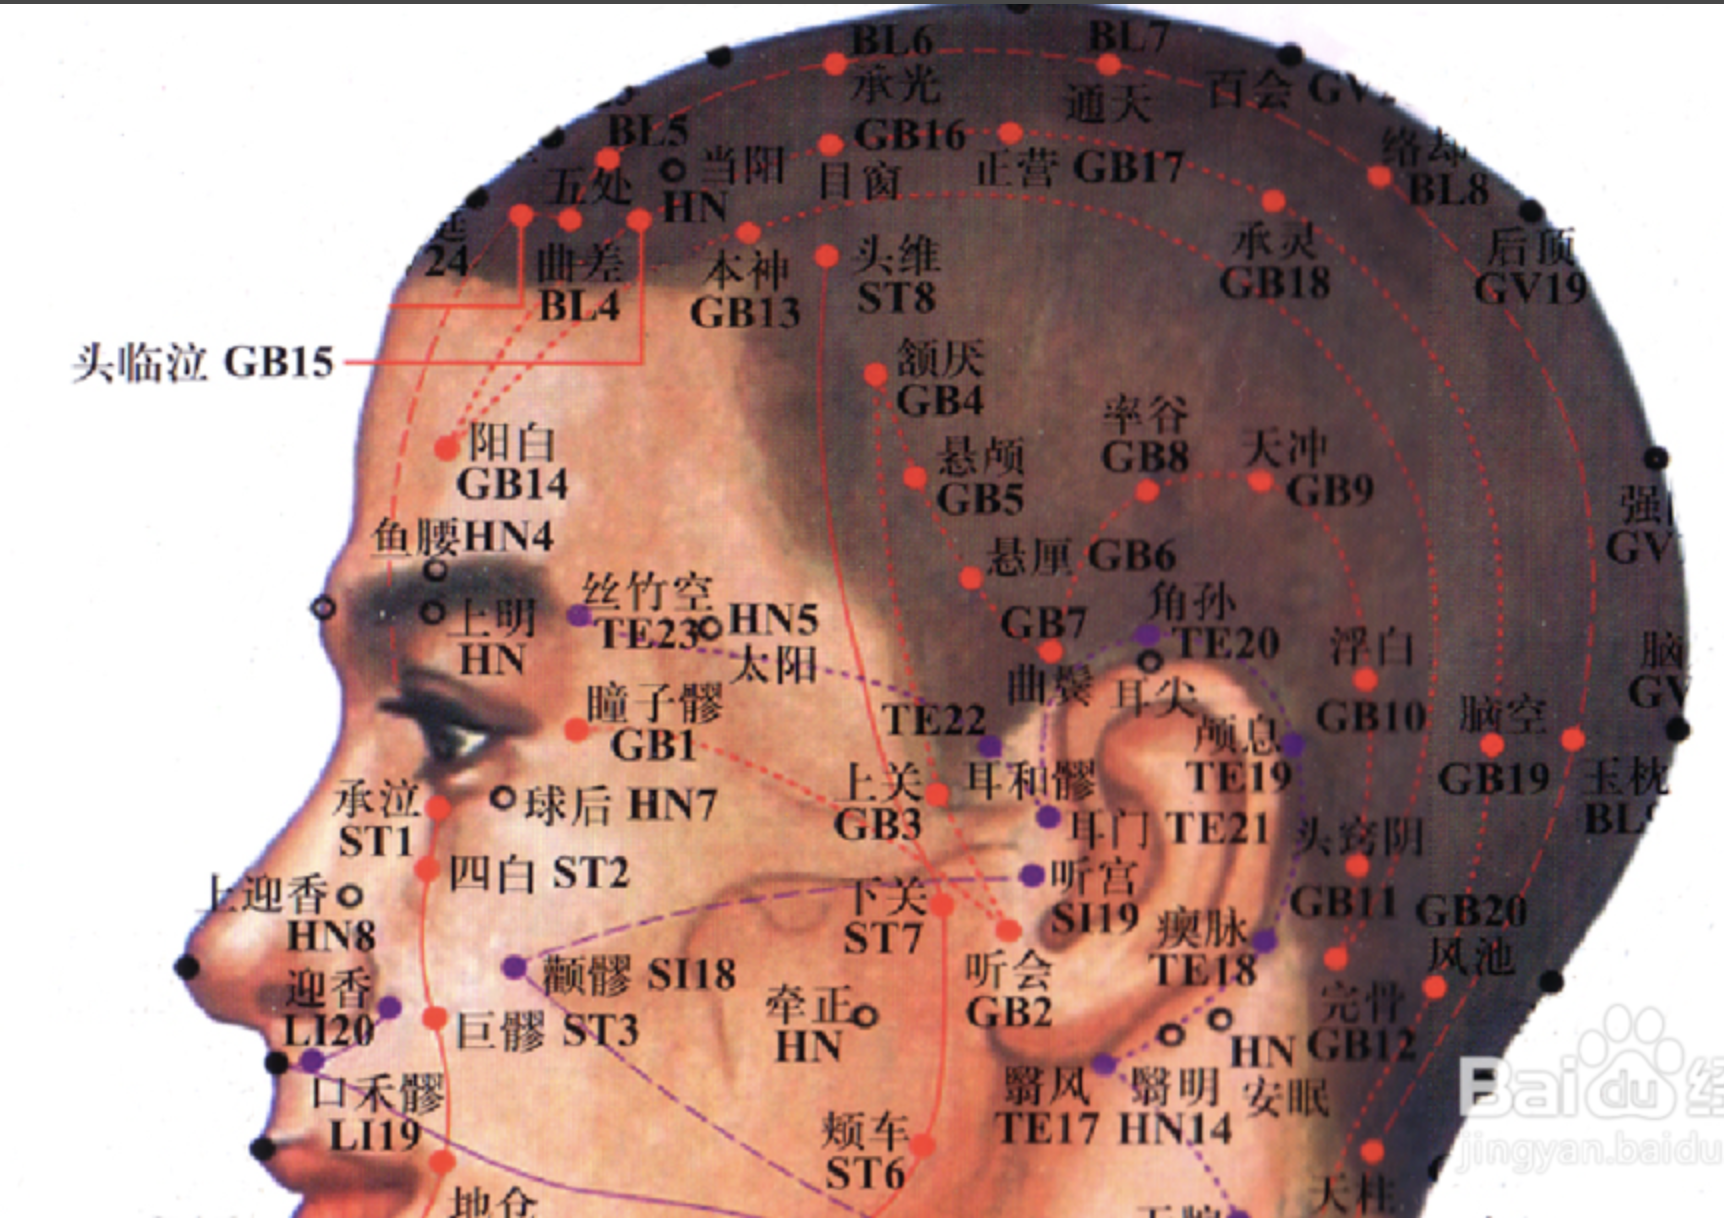

瞳子髎(liáo)

【定位】 在面部,目外眦旁 0.5 寸,当眶外侧缘处。

【主治】 头痛,目赤,目痛,畏光,迎风流泪,远视不明,内障,目翳。

【配伍】 配合谷、临泣、睛明治目生内障,配少泽治妇人乳肿,配养老、肝俞、光明、太冲、治疗视物昏花。

【刺灸法】 向后刺或斜刺 0.3 ~ 0.5 寸;或用三棱针点刺出血。

【附注】 手太阳,手、足少阳之会。

阳白

【定位】 在前额部,当瞳孔直上,眉上 1 寸。

【主治】 头痛,目眩,目痛,外眦疼痛,雀目。

【配伍】 配太阳、睛明、鱼腰治目赤肿痛、视物昏花、上睑下垂。

【刺灸法】 平刺 0.5 ~ 0.8 寸;可灸。

【附注】 足太阳、阳维之会。

头临泣

【定位】 在头部,当瞳孔直上入前发际 0.5 寸,神庭与头维连线的中点处(图 10-29-2)。

【主治】 头痛,目眩,目赤痛,流泪,目翳,鼻塞,鼻渊,耳聋,小儿惊痫,热病。

【配伍】 配阳谷、腕骨、申脉治风眩,配肝俞治白翳,配大椎、腰奇、水沟、十宣治中风昏迷,癫痫,配大椎、间使、胆俞、肝俞治疟疾。

【刺灸法】 平刺 0.5 ~ 0.8 寸;可灸。

【附注】 足太阳、少阳、阳维之会。

风池

【定位】 在项部,当枕骨之下,与风府相平,胸锁乳突肌与斜方肌上端之间的凹陷处。

【主治】 头痛,眩晕,颈项强痛,目赤痛,目泪出,鼻渊,鼻衄,耳聋,气闭,中风,口眼歪斜,疟疾,热病,感冒,瘿气。

【配伍】 配合谷、丝竹空治偏正头痛,配脑户、玉枕、风府、上星治目痛不能视,配百会、太冲、水沟、足三里、十宣治中风。

【刺灸法】 针尖微下,向鼻尖方向斜刺 0.5 ~ 0.8 寸,或平刺透风府穴;可灸。

【附注】 足少阳、阳维之会。